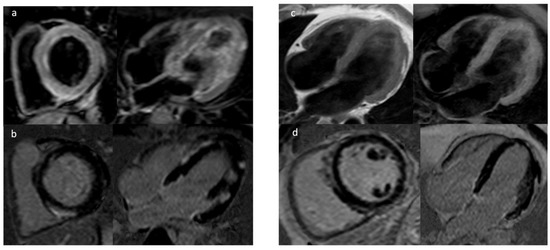

4.1. Late Gadolinium Enhancement

4.2. Mapping Techniques and Extracellular Volume

4.3. Feature Tracking (FT)

4.4. CMR in Mitral Valve Prolapse

| LGE | Fibrosis | ICM, NICM HCM, Myocarditis ARVC, LVNC Mitral valve prolapse | Independent predictor for VA and SCD |

| T1 and ECV | Tissue edema and diffuse fibrosis | ICM, NICM HCM, Myocarditis | Higher native T1 values associated with VA |

| T2 | Myocardial edema | Myocarditis | Abnormal T2 mapping is involved in predicting major adverse events including cardiac death |

| LVEF | Left ventricular systolic function | ICM, NICM Myocarditis, ARVC LVNC | LV systolic dysfunction is associated with an increased risk of SCD |

| RVEF | Right ventricular systolic function | ARVDC | Overall increase in VA in RV dysfunction |

| Strain Imaging and MD | Myocardial deformation and function | ICM, NICM | Impaired strain associated with SCD |